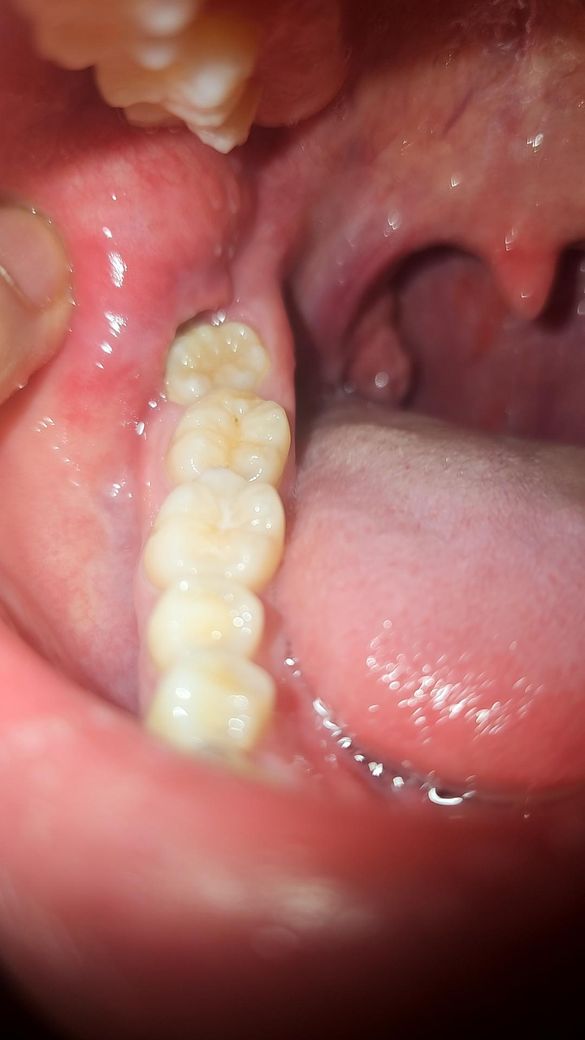

• 2번 째 사진

사랑니 때문에 염증이 생겨서 불편한거 같습니다. 계속 불편하시면 사랑니 발치를 하시는게 좋을것같습니다.

사랑니로 인해서 잇몸에 염증을 유발한다면 사랑니를 발치해주는 것이 좋습니다. 지속적으로 염증을 유발하게 되면 주변 조직에 손상이 발생할 수 있기 때문입니다